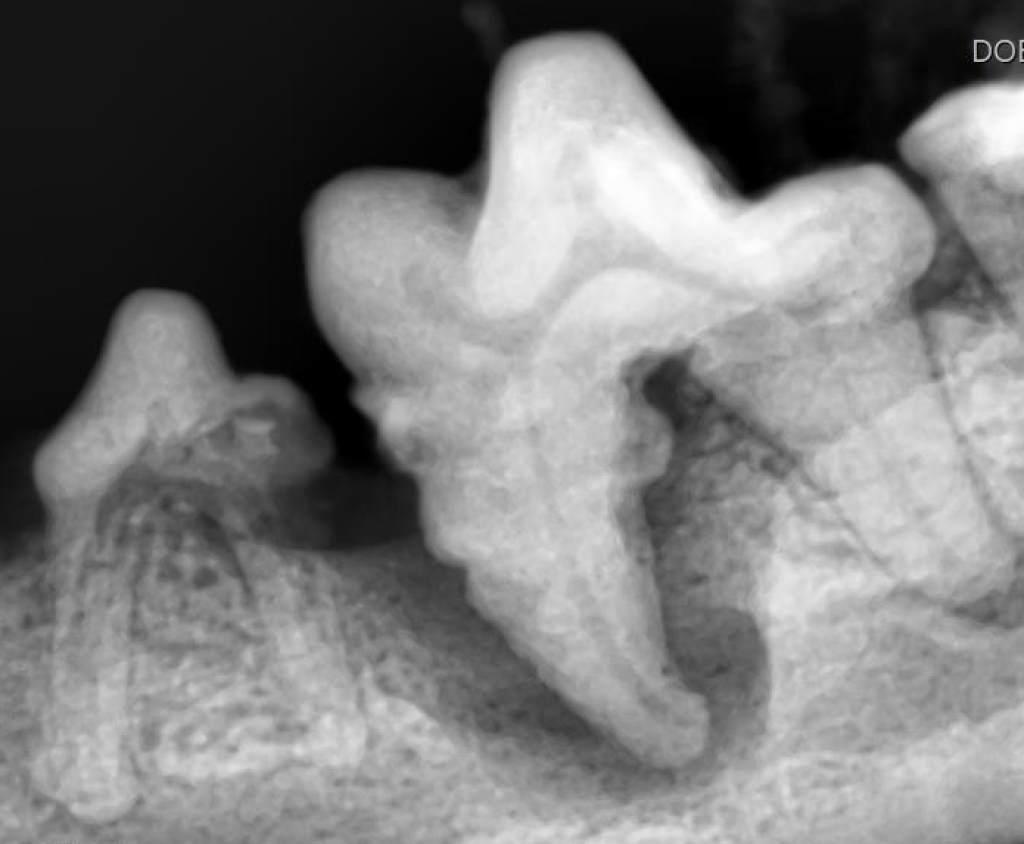

下の写真を見てみましょう。

下顎の第一後臼歯に歯石が沈着し、歯肉が後退しているのが分かります。

沈着している歯石を除去すると、歯根が見えるほど歯槽骨が融解していることが分かりました。

歯科レントゲンを撮ってみると歯を支える歯槽骨が重度に融解しており、重度歯周病と診断しました。